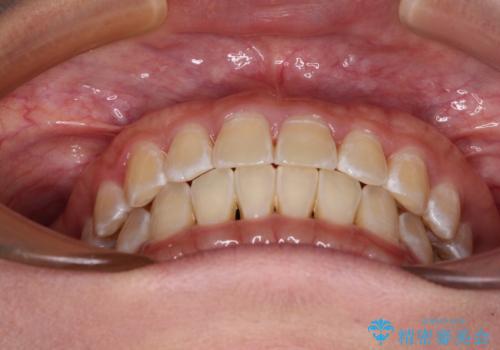

前歯の隙間と上下正中のズレを解消

- 上下前歯隙間と正中のズレを改善したいとのことで来院された患者様です。

自己管理を減らしたいとのことで、ワイヤー装置による矯正治療を行うこととしました。

正中がなかなか合わずに、2年近くの治療期間を要しました。